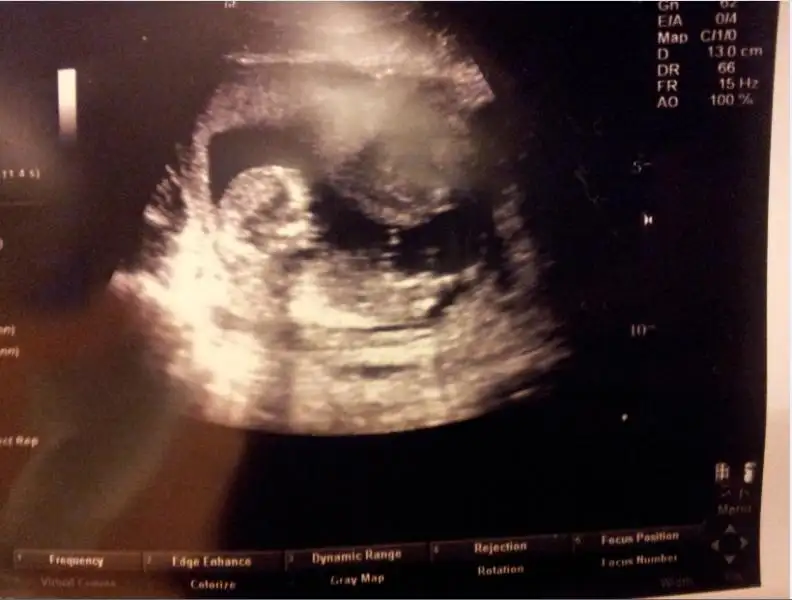

Merhaba kızlar.biz de 12+1 haftalığız.benim ultrason sonucuma da bakabilir misiniz?Eki Görüntüle 857572 Eki Görüntüle 857571